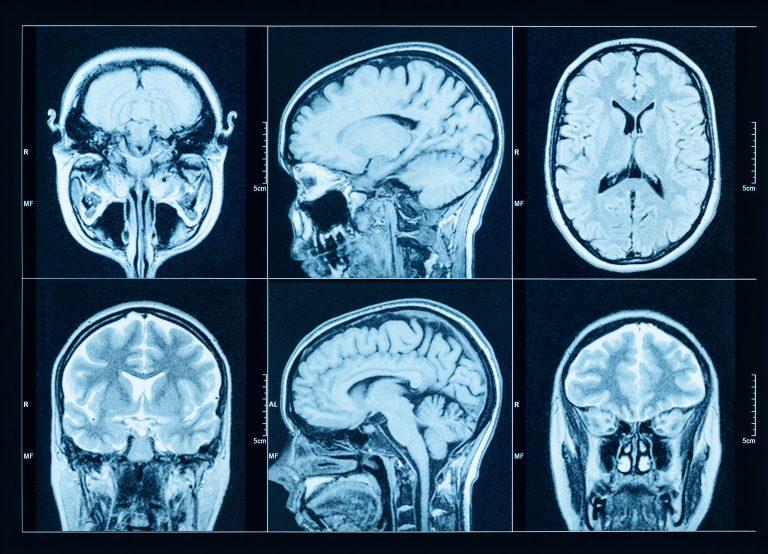

Chụp cộng hưởng từ (MRI) chuyên sâu

MRI truyền thống thường chỉ dùng để loại trừ các tổn thương cấu trúc. Tuy nhiên, các kỹ thuật MRI hiện đại (như MRI 3.0 Tesla) có thể quan sát dấu hiệu "Đuôi chim én" (Swallow-tail sign).

Sự biến mất của dấu hiệu này ở vùng chất đen là một chỉ báo quan trọng cho bệnh Parkinson.

Chụp MRI não: Loại trừ các nguyên nhân gây ra triệu chứng "giống Parkinson".